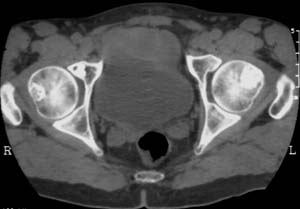

男,61岁,左侧髋关节疼痛,负重后更明显

现上传ct片

左侧股骨头增密,其内见有囊变密度减低区,关节面骨质硬化,关节间隙及髋臼无异示。考虑股骨头缺血坏死可能。建议mri检查。

我觉得股骨头未见到明显的问题,左侧股骨颈有卵圆形高密度影,考虑骨岛或骨梗死。

1\\左侧股骨颈有卵圆形高密度影,考虑骨岛或骨梗死。2\\由于临床症状疼痛,应该mri检查排除早期股骨头缺血坏死

左侧股骨颈处一卵圆形密度增高影,边界清,临近骨组织未见明显破坏.考虑为骨梗死,骨岛?